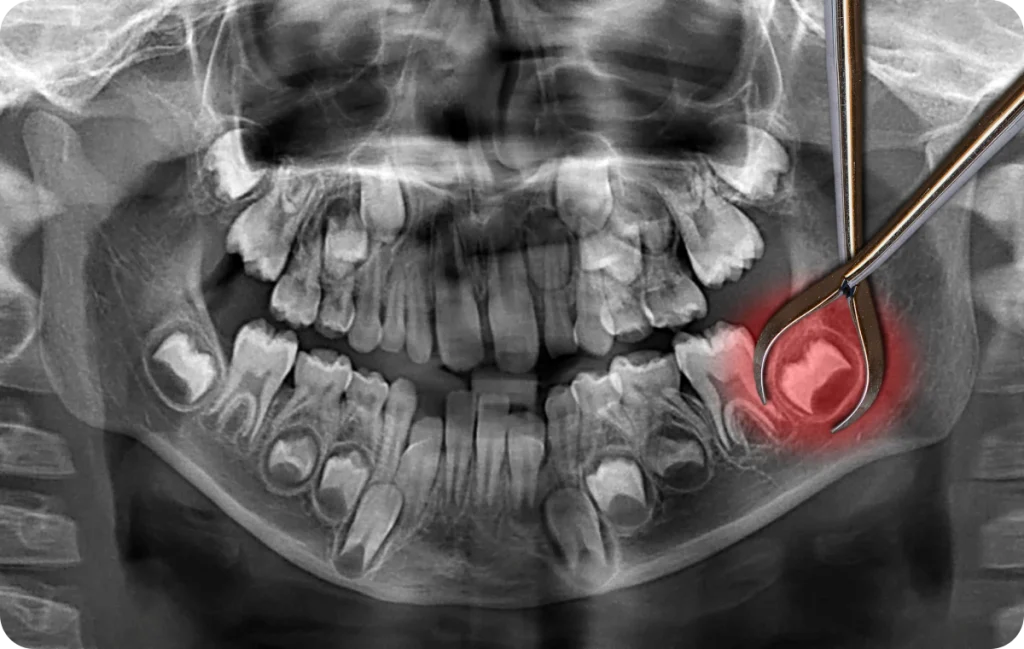

Le dentiste évalue toujours la situation grâce à une radiographie panoramique. Cet examen montre la position exacte des racines et leur proximité avec le nerf mandibulaire.

Avant toute intervention, le dentiste effectue un bilan complet. Il examine la bouche, prend une radiographie panoramique et explique les étapes du traitement. Cette préparation permet de rassurer le patient et d’anticiper les particularités anatomiques.